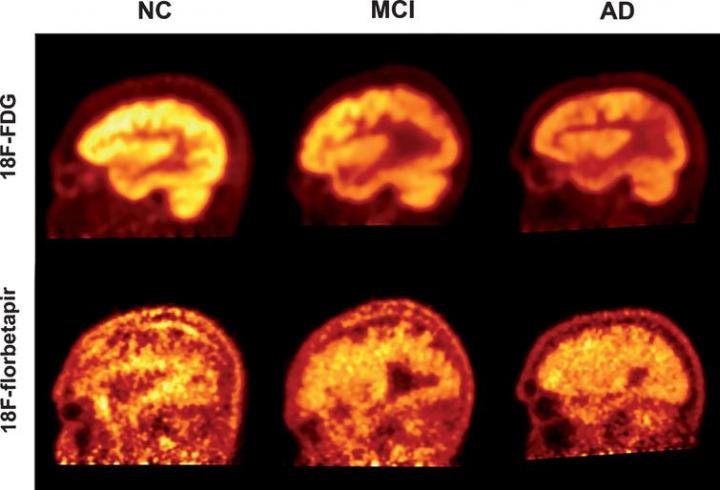

Confronto tra scansioni PET con radiotraccianti FDG e florbetapir per quantificare il declino cognitivo nei pazienti di Alzheimer (AD), lieve deficit cognitivo (MCI) e controlli sani (NC). Fonte: Penn Medicine.

I ricercatori hanno concluso che la PET con fluorodeossiglucosio (FDG), che misura il consumo di glucosio nel cervello come marcatore di attività neurale, è un approccio più potente per valutare la progressione e la gravità del MA e del lieve decadimento cognitivo (MCI, mild cognitive impairment) rispetto alle scansioni PET con florbetapir, che rivelano depositi di proteine amiloidi nel cervello.

Due dei biomarcatori più significativi riscontrati nel MA sono la riduzione dell'assunzione di glucosio e l'accumulo di placche amiloidi nel cervello. Le scansioni PET usano diversi farmaci radioattivi, chiamati radiotraccianti, per misurare questi biomarcatori all'interno del tessuto cerebrale dei pazienti con deficit cognitivo. La FDG-PET è una delle tecniche di scansione più usate per diagnosticare il MA. Tuttavia, negli ultimi anni, sono stati sviluppati diversi altri radiotraccianti, come il florbetapir, per rilevare la deposizione di placche amiloidi.

Lo studio ha rivelato che le scansioni PET, sia con FDG che con florbetapir, sono in grado di discriminare efficacemente gli individui con demenza dal gruppo di controllo sano. Tuttavia, rispetto ai punteggi MMSE, la correlazione tra basse prestazioni cognitive e alti livelli di amiloide era significativamente più debole della correlazione tra FDG e basse prestazioni cognitive per tutti i gruppi inclusi nello studio. Ciò suggerisce che la FDG-PET è un indicatore più sensibile del declino cognitivo.